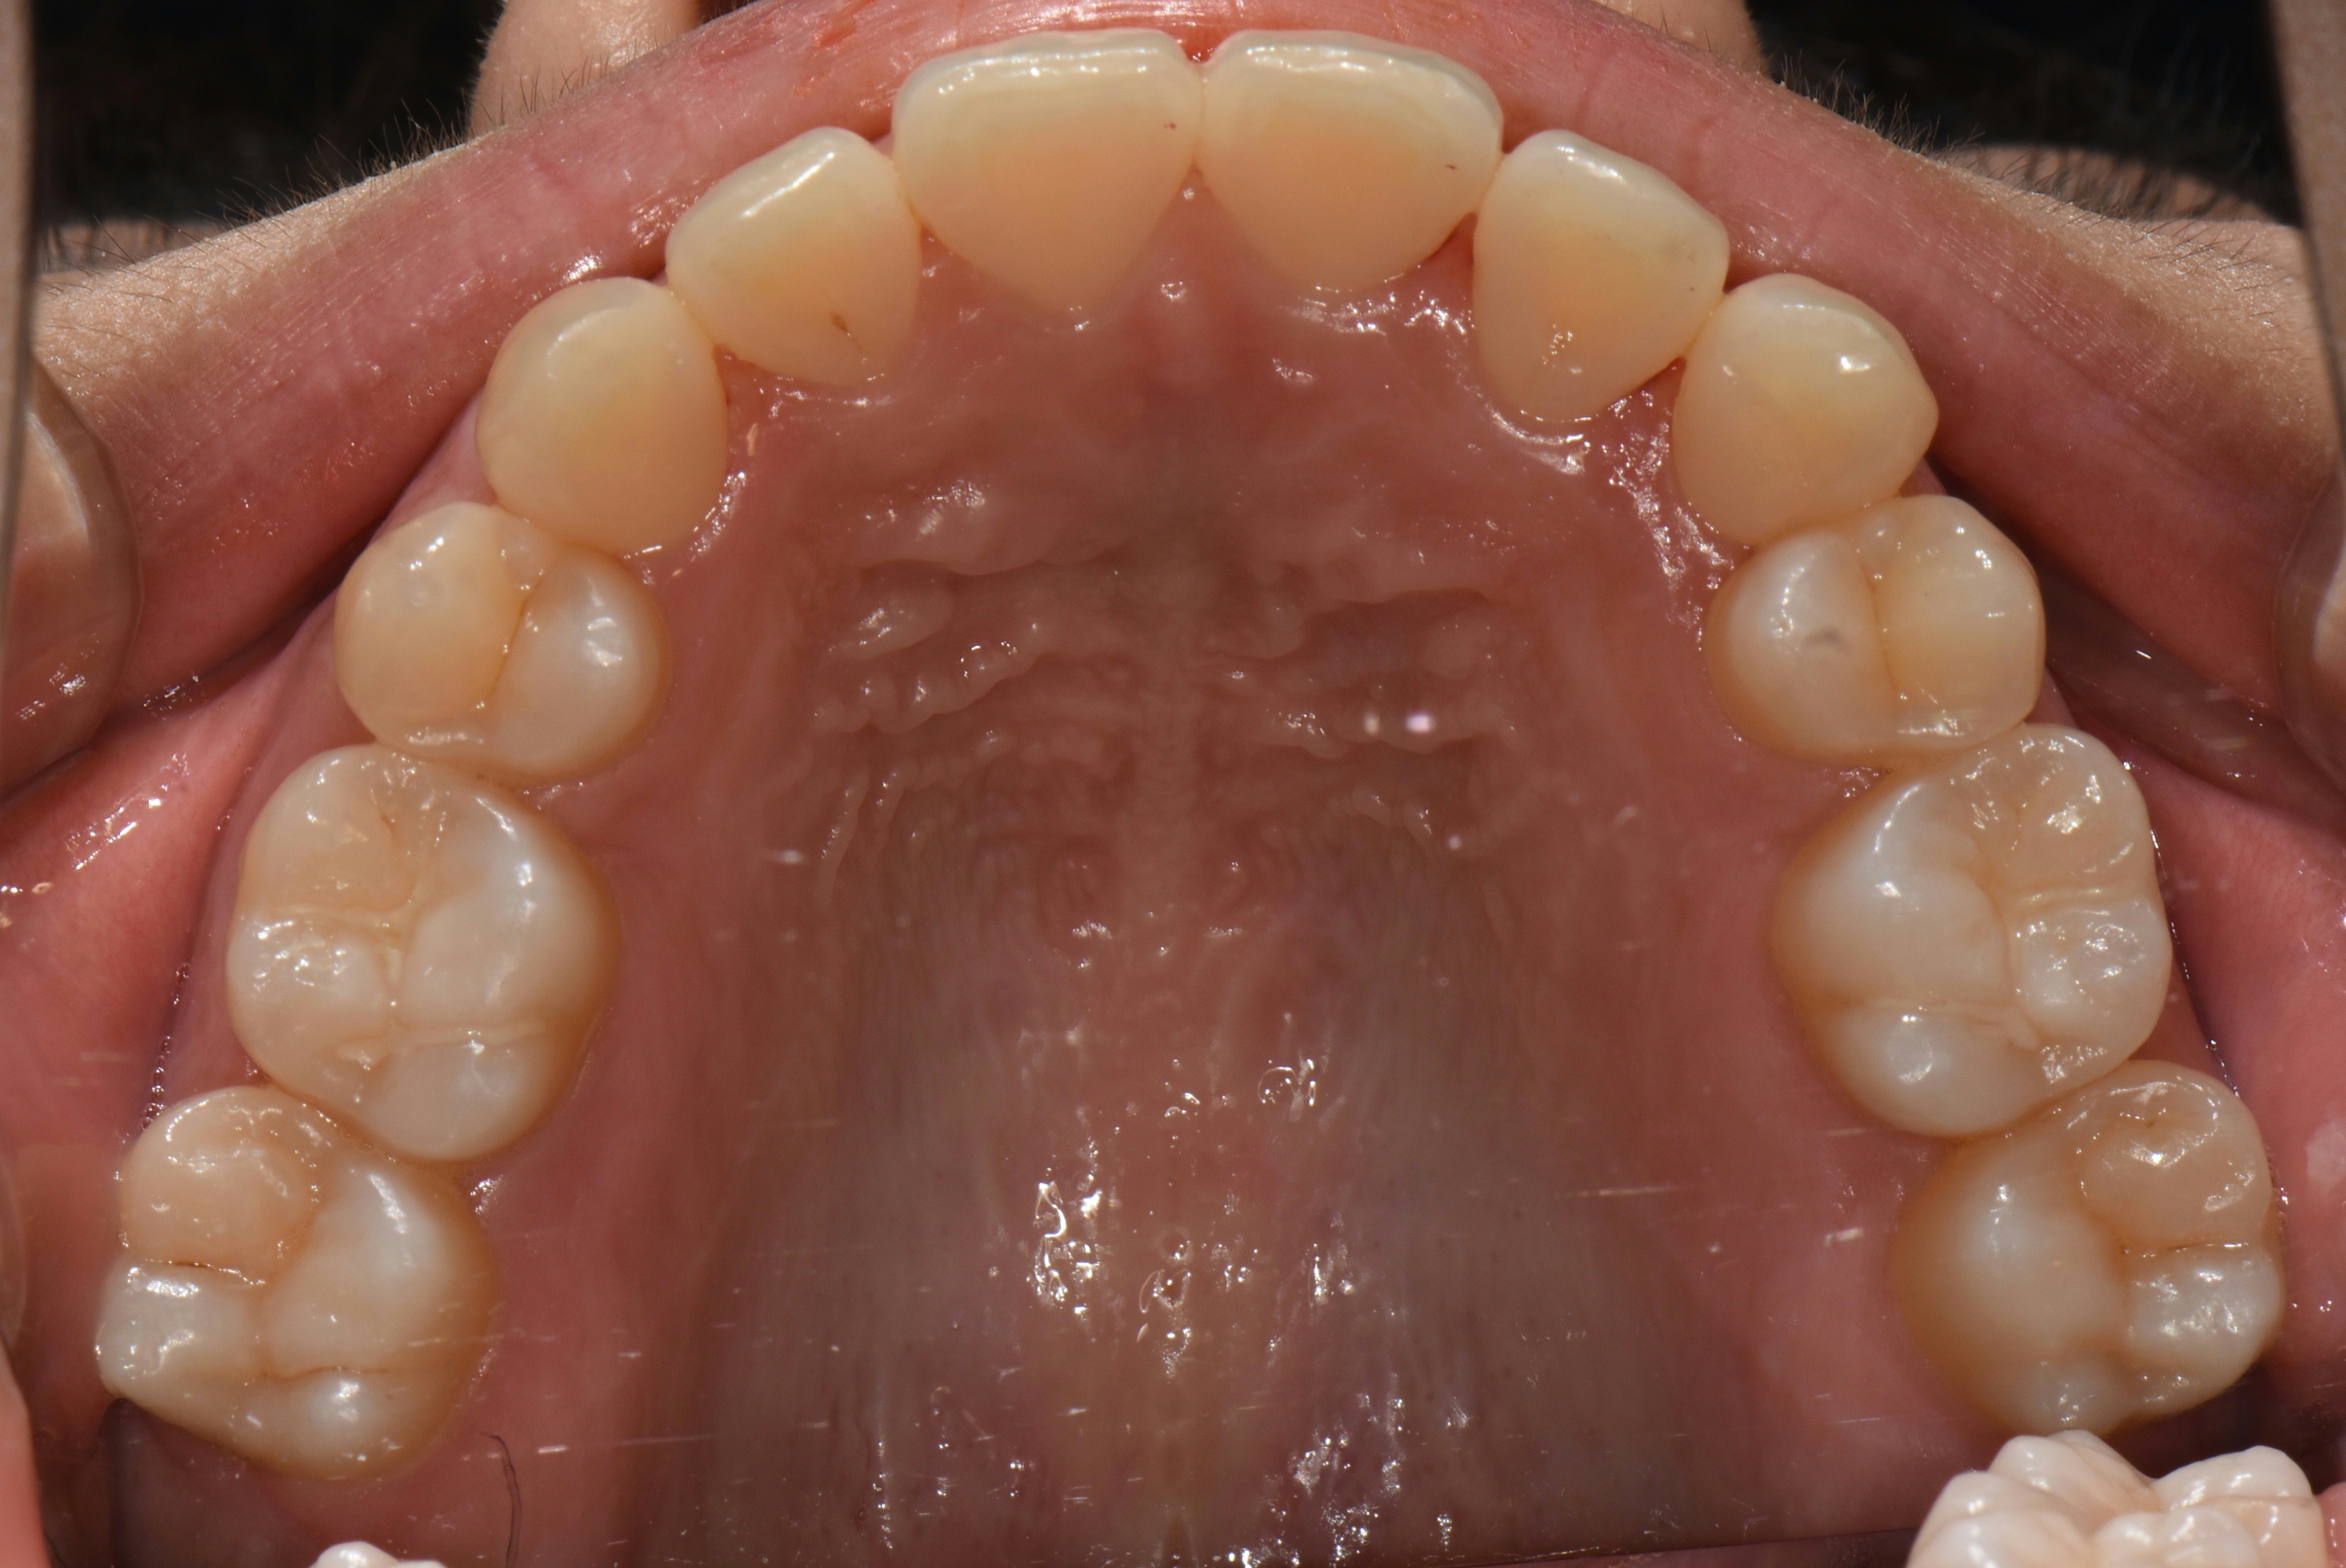

치료 전 사진입니다.